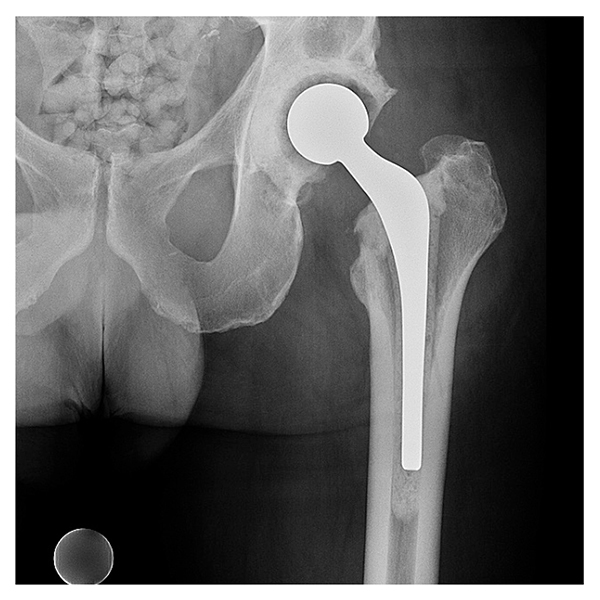

The components were safely removed without a trochanteric osteotomy. The anterior incision was included within the sterile field so that it could be debrided, and the anterior interval was identified from the posterior approach. Scrub brushes with 10% povidone iodine were used to debride the posterior and anterior tracts and the bony surface; the wound was irrigated and immersed in 10% povidone iodine for 10 minutes, and an articulating spacer with antibiotic cement (high-viscosity Palacos [R+G] cement containing gentamicin 0.5 g and vancomycin 2 g) was placed (Fig. 2).

Figure 2: Postoperative radiograph demonstrating an articulating hip spacer with a semi-constrained acetabular component and femoral component made intraoperatively from a mold.